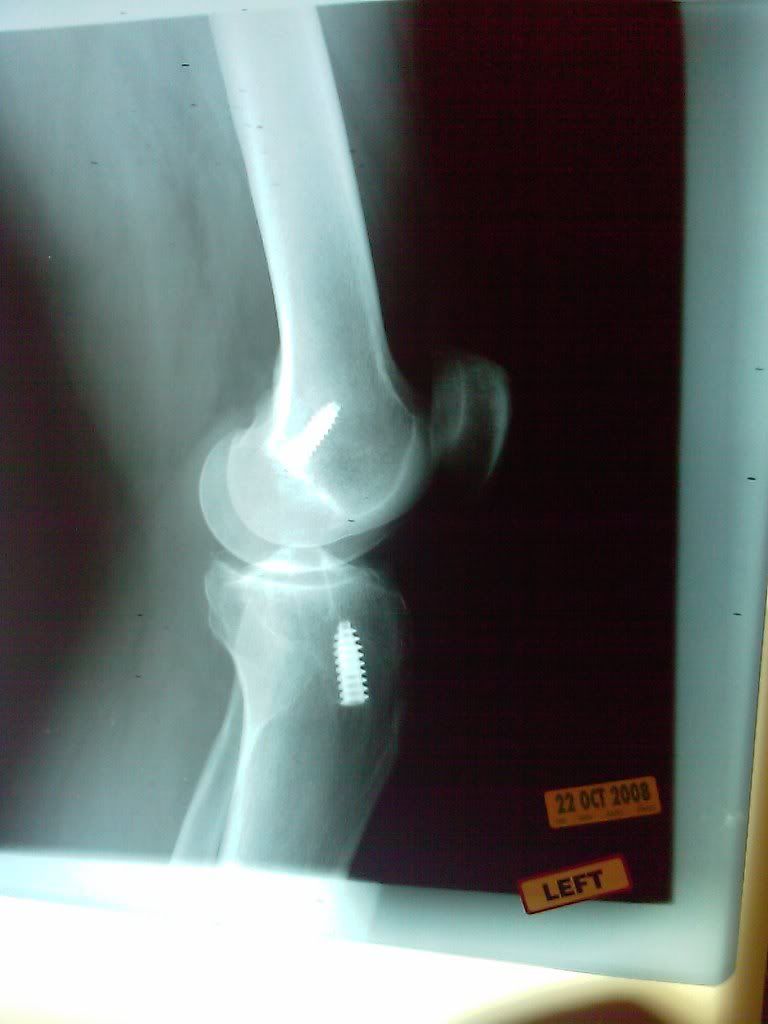

Screws In Left Knee After ACL Surgery 3 Photo by FastRX8 Photobucket Are Screws Used In Knee Replacement Surgery knee replacement surgery. total knee replacement is one of the most commonly performed joint replacement surgeries. the surgeon makes a cut down the front of your knee and moves your kneecap to the side so they can get to the knee joint. Artificial knee joints used in knee replacement surgery are typically made of. in some. Are Screws Used In Knee Replacement Surgery.